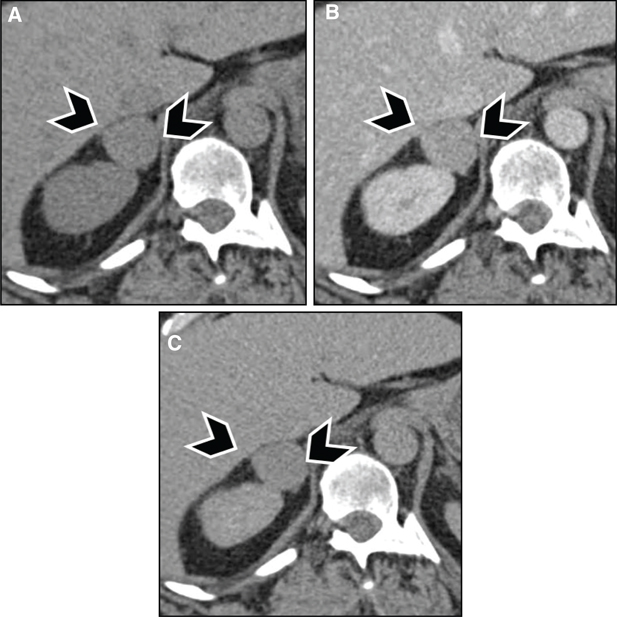

With contrast administration, PPGLs tend to enhance rapidly and avidly due to a rich capillary network (Figures 3 and 4). Adrenal adenomas usually demonstrate milder enhancement than pheochromocytomas or malignant tumors but have faster washout. Absolute washout of more than 60% or relative washout of more than 40% has been previously accepted as being characteristic of benign adrenal adenoma, although more recent studies have suggested that a good proportion of pheochromocytomas, potentially up to one-third, can have washout characteristics similar to benign adenomas (20, 21).

Fig 3

Figure 3 Pheochromocytoma in a 39-year-old male patient with neurofibromatosis type 1. (A) Noncontrast images demonstrate a hypodense lesion in the right adrenal gland (arrowheads), with (B) marked enhancement after contrast administration. (C) Adrenal washout phase acquired 15 min after contrast administration demonstrates rapid washout, which is usually seen with adrenal adenomas but can be seen in one-third of pheochromocytomas. The patient had elevated metanephrines, and surgical pathology was consistent with pheochromocytoma.

Fig 4

Figure 4 Paraganglioma in a 30-year-old male patient. Images obtained after administration of iodinated intravenous contrast demonstrate heterogeneously hyperenhancing retroperitoneal mass compressing the right renal vein (white arrow) with prominent vascular feeders (arrowheads) and a peripheral calcification (black arrow).